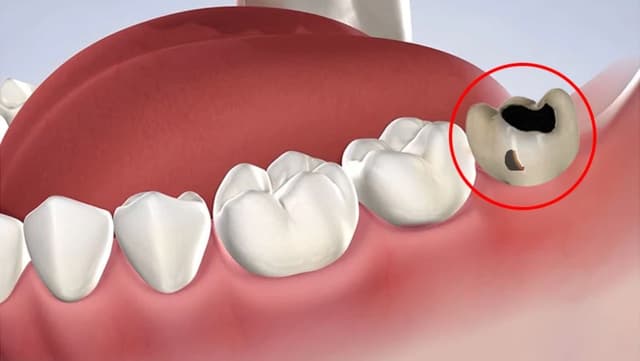

Giải mã 5 lý do không nên chần chừ khi nhổ răng khôn bị sâu

Nên xử lý thế nào nếu răng khôn bị sâu? Nhiều người nghĩ rằng chỉ cần trám là đủ, nhưng sự thật lại hoàn toàn khác. Khi răng khôn bị sâu, nó không chỉ đơn thuần là một chiếc răng sâu bình thường mà còn là “quả bom hẹn giờ” trong khoang miệng, tiềm ẩn […]